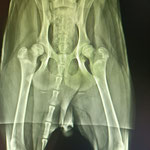

Tubbi a besoin de beaucoup d'amour et de contacts pour panser son doux cœur meurtri mais Tubbi aura sans doute aussi besoin de suivi et de soins pour sa dysplasie. Car ce brave chien a grandi très vite, sans doute mal nourri et surtout sans le moindre exercice. Son ossature s'est développée mais pas sa musculature. Il ne souffre pas car c'est un très jeune chien mais en prenant de l'âge des douleurs peuvent s'installer.